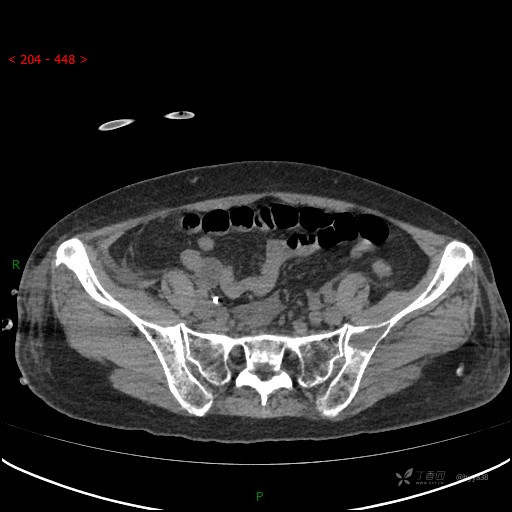

CT平扫